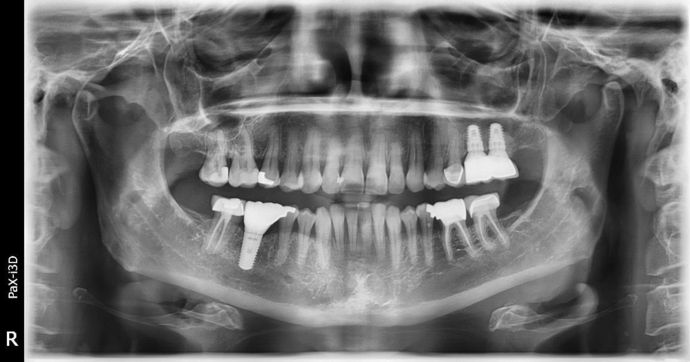

Dental Implants: Case 3 - Freeport

2 implants were placed on the upper left side, we had very little bone to work with. A 6 mm sinus augmentation was needed on the back implant and a 4 mm augmentation was needed on the more forward one. We did all of that at the time of implant placement here at the office. We finished the case using a fixed bridge to more evenly spread the load, we have a ton of bone that can be seen around the implants and it is still calcifying/healing towards the tops of the implants! I love complicated surgical cases like this, there is such a sense of accomplishment! I'll just borrow a saying here: WINNING!